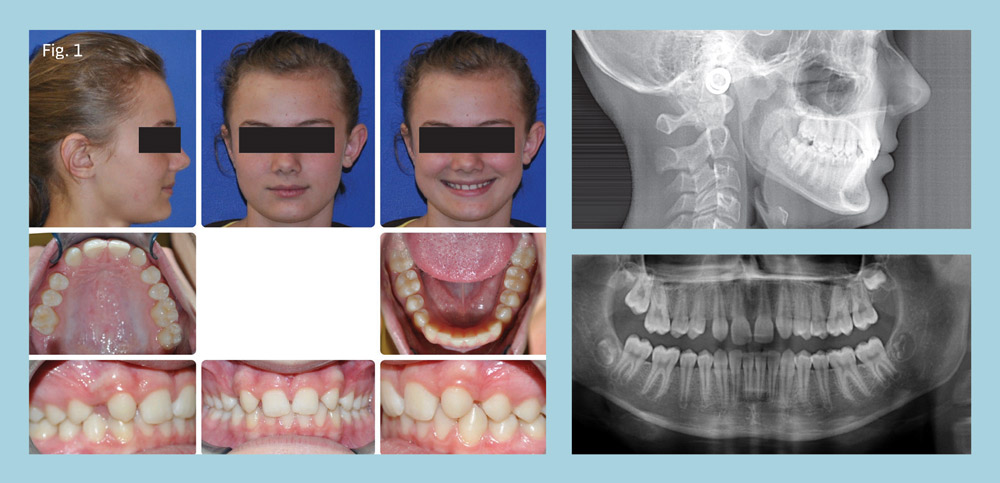

Our 11-year-old patient presented with congenitally missing teeth 7 and 10, skeletal Class I, dental Class II subdivision left, retro-inclined/upright maxillary incisors, good facial balance, and lip posture with a slightly obtuse nasolabial angle (Fig. 1).

At the consultation, her mother said that she didn't want implants or false teeth for her daughter, and instead requested that all space be closed. A canine replacement of missing laterals would be particularly challenging because the maxillary incisors were already retro-inclined, and a solid Class I molar was already present on the right side.